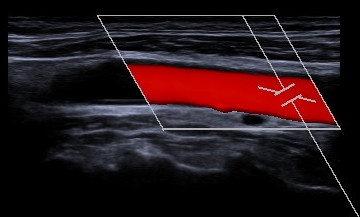

Gefäßdarstellung mittels Ultraschall

Bei der Doppler-Duplex-Sonographie der Halsgefäße wird untersucht, ob Verkalkungen (Plaques) vorliegen, und ob es dadurch zu Verengungen (Stenosen) kommt.

Neben dem Aussehen der Plaques wird die lokale Flussgeschwindigkeit des Blutes beurteilt: Je schneller die Flussgeschwindigkeit, desto hochgradiger die Stenose.